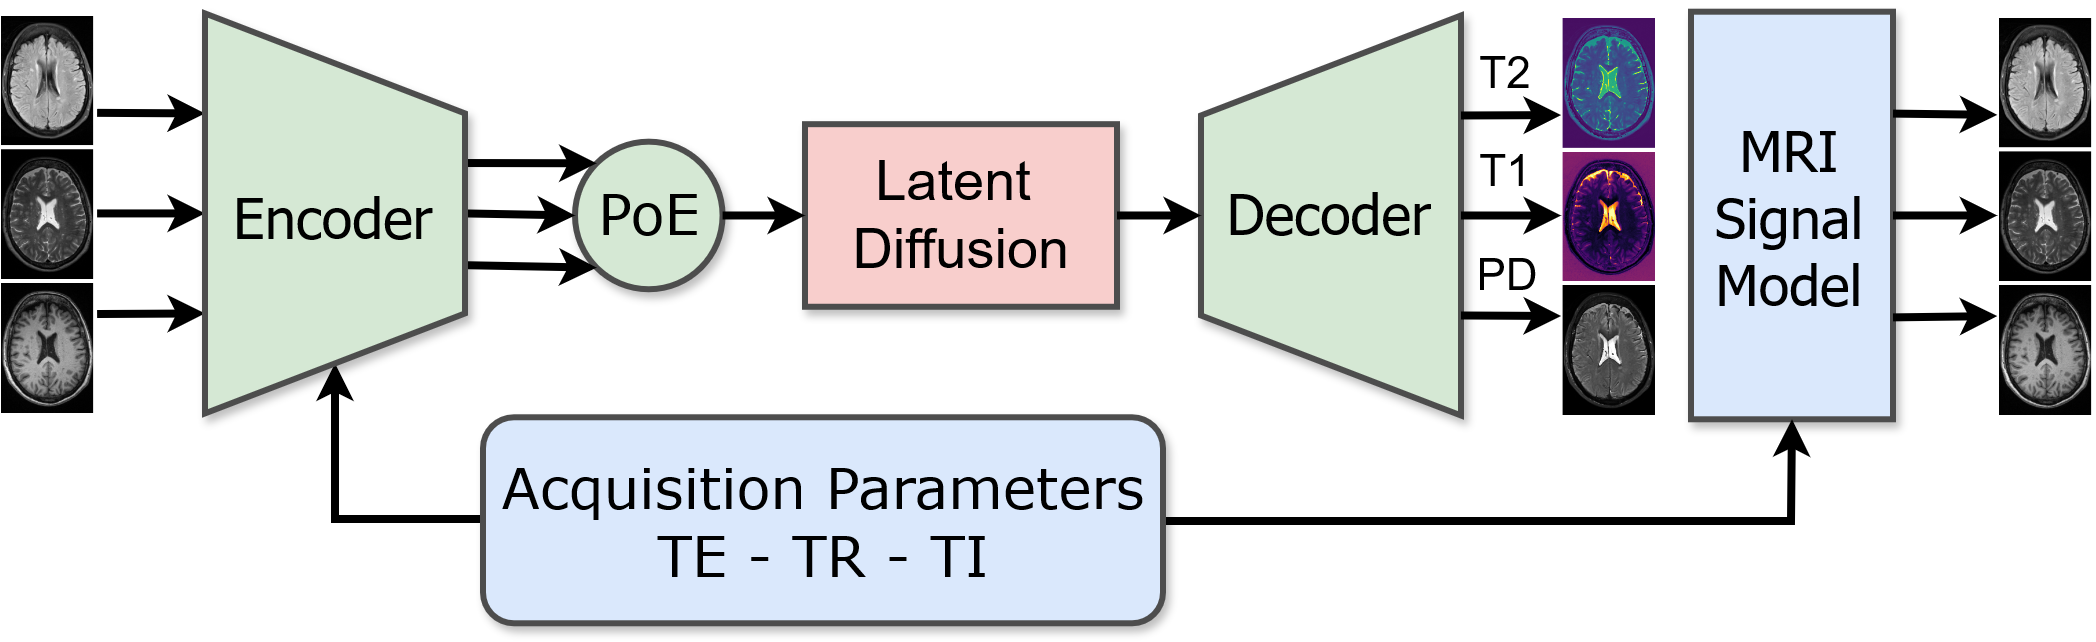

In this paper, we propose a novel physics-informed diffusion-based generative model for multimodal brain MR scans. Inspired by quantitative MRI techniques [13, 12], we utilize the acquisition parameters [6] in combination with a physical signal model [2] and a latent diffusion model to synthesize images in a two-step process: (1) The generation of modality shared physical tissue property maps, namely the proton density, the longitudinal relaxation time, and the transverse relaxation time, (2) The application of a physical signal model with a desired set of scanner acquisition parameters to the tissue property maps to obtain the final MRI scan.

2.2 Multimodal Physics-Informed Variational Autoencoder

To efficiently perform denoising diffusion to generate tissue property maps containing PD, T1, and T2, we design a multimodal physics-informed variational autoencoder that downsamples multimodal MRI scans by a factor of 8 into a shared lower dimensional latent representation.

We use a single shared convolutional encoder to encode the input modalities independently into unimodal latent distributions . The encoder is conditioned on the acquisition parameters corresponding to each input image using adaptive group normalization [7] in the residual blocks:

To combine the unimodal latent distributions into a shared multimodal distribution , we use a product-of-experts:

We decode the shared latent representation using a convolutional network into tissue property maps by passing its output through the exponential function, ensuring that the property values are greater than zero, and transforming the resulting values by the signal model (Equation 1) to reconstruct the input. Following previous work [20, 18], we combine an L2 reconstruction loss with a perceptual loss, a patch-wise adversarial loss, and a KL-regularization loss on the latent distribution.

2.3 Latent Diffusion Model

To generate new tissue properties maps, we train a latent diffusion model [20] on the joint multimodal representation we obtain through Equation 3. Given a sample , the objective function is: